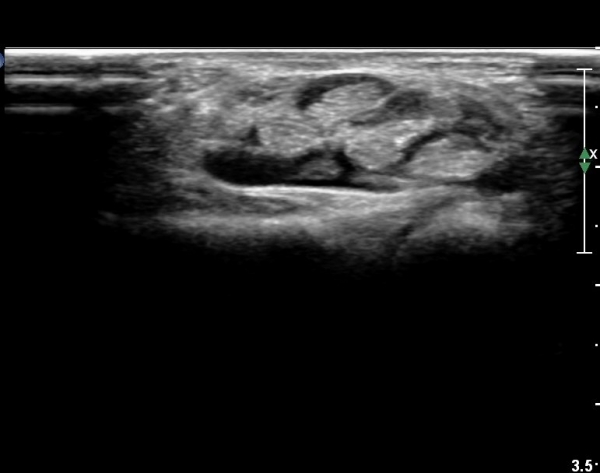

µµÇ÷¯°Ë»ç¿¡¼­ Ç÷·ùÁõ°¡°¡ °üÂûµÈ´Ù(»çÁø 2).